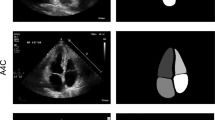

Deep learning algorithms for left ventricle (LV) segmentation are prone to bias towards the training dataset. This study assesses sex- and age-dependent performance differences when using deep learning for automatic LV segmentation. Retrospective analysis of 100 healthy subjects undergoing cardiac MRI from 2012 to 2018, with 10 men and women in the following age groups: 18–30, 31–40, 41–50, 51–60, and 61–80 years old. Subjects underwent 1.5 T, 2D CINE SSFP MRI. 35 pathologic cases from local clinical exams and the SCMR 2015 consensus contours dataset were also analyzed. A fully convolutional network (FCN) similar to U-Net trained on the U.K. Biobank was used to automatically segment LV endocardial and epicardial contours. FCN and manual segmentation were compared using Dice metrics and measurements of end-diastolic volume (EDV), end-systolic volume (ESV), mass (LVM), and ejection fraction (LVEF). Paired t-tests and linear regressions were used to analyze measurement differences with respect to sex and age. Dice metrics (median ± IQR) for n = 135 cases were 0.94 ± 0.04/0.87 ± 0.10 (ED endocardium/ES endocardium). Measurement biases (mean ± SD) among the healthy cohort were − 0.3 ± 10.1 mL for EDV, − 6.7 ± 9.6 mL for ESV, 4.6 ± 6.4% for LVEF, and − 2.2 ± 11.0 g for LVM; biases were independent of sex and age. Biases among the 35 pathologic cases were 0.1 ± 19 mL for EDV, − 4.8 ± 19 mL for ESV, 2.0 ± 7.6% for LVEF, and 1.0 ± 20 g for LVM. In conclusion, automatic segmentation by the Biobank-trained FCN was independent of age and sex. Improvements in end-systolic basal slice detection are needed to decrease bias and improve precision in ESV and LVEF.